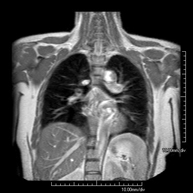

- Chest MRI

This non-invasive diagnostic procedure uses an electromagnetic field and radio waves (from a transmitter and receiver) to acquire high-definition anatomical images of the chest. It is a radiation-free procedure. It is indicated for lung lesions in which infiltration of the mediastinum or thoracic wall must be ruled out, to differentiate between solid and cystic chest lesions, etc. Sometimes paramagnetic contrast (gadolinium) must be used to complete the study.